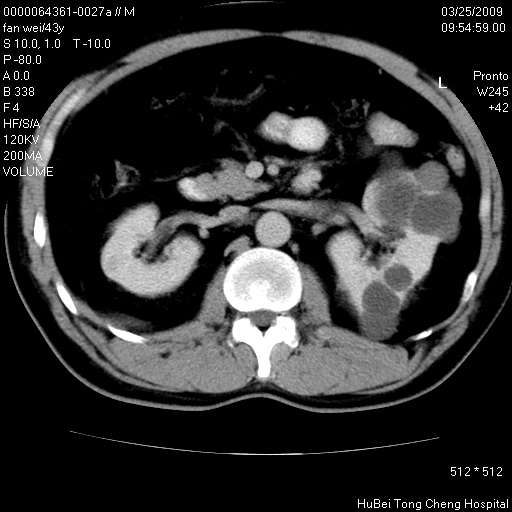

患者 男,43岁。左侧腰部不适两天。平素健康。无家族遗传病史。

双肾ct轴位平扫+增强扫描(层厚10mm,螺距1.0,重建间隔10mm),图像如下:

左肾体积变大,支持多囊肾。

双侧多囊肾!

双肾多发性囊肿   脂肪肝

囊肿数得清,肾功能正常,考虑多发肾囊肿.另外,右肾后极突向肾周间隙的那个病灶是不是错构瘤,请楼主调窗看看.